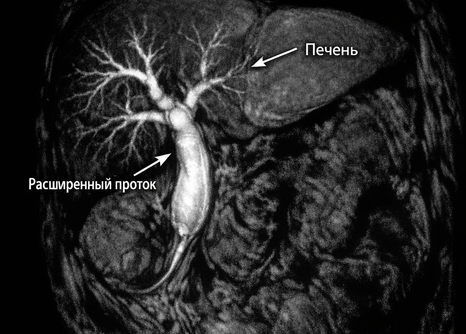

Инструментальная диагностика: УЗИ, КТ, МРТ, ЭРПХГ и их роль

Применение различных методов визуализации

Инструментальные методы позволяют визуализировать желчный пузырь и протоки:

• УЗИ органов брюшной полости: первый этап скрининга. Позволяет выявить расширение протоков и наличие камней.

• КТ и МРТ: дают более детальную информацию о структуре печени и поджелудочной железы.

• МРХПГ (магнитно-резонансная холангиопанкреатография): «золотой стандарт» неинвазивной визуализации желчных путей.